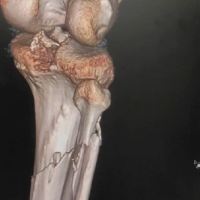

A 3-year-old female was brought to the pediatric orthopedic department with complaints of swelling over her left leg for 2 months. The swelling was insidious in onset, progressive in nature, associated with pain which was aggravated by movement, more at night, and associated with fever and local rise of temperature. According to the mother, weight loss and loss of appetite were noted. No history of abdominal pain. An X-ray of the left thigh was requested. It revealed an ill-defined subtle expansile lytic lesion in the diaphysis and distal metaphysis region of the left femur with the suggestion of lamellated (onion peel) and sunburst (in a few areas) types of periosteal reaction (Fig. 1). No evidence of fracture was noted. Laboratory results were as follows; white blood cell – 7220 cells/μL, hemoglobin – 6.8 g/dL (decreased), hematocrit – 24%, platelets – 190,000/μL, C-reactive protein (CRP) – 81.5 mg/L (raised) and lactate dehydrogenase (LDH) – 467.99 U/L (raised). The differential diagnosis of primary bone tumor (Ewing’s sarcoma > osteosarcoma) and osteomyelitis was considered initially. (High Resolution Sonography)left thigh was done, which revealed soft tissue showing significant vascularity on color Doppler with associated spiculated sunburst type of periosteal reaction (Fig. 2). A provisional diagnosis of primary bone tumor was made and as a part of metastatic screening, ultrasonography of the abdomen was advised. It revealed a large ill-defined heterogeneous retroperitoneal mass crossing the midline, encasing the aorta and its branches. The mass was seen insinuating beneath the aorta, lifting it off the vertebral column. Multiple enlarged pre/para-aortic lymph nodes and bilateral common, external, and internal iliac vessels were noted (Fig. 3). To further characterize the abdominal mass, the contrast-enhanced computed tomography (CECT) chest with the abdomen covering the thigh was done. It revealed a large heterogeneous solid mass lesion epicenter in the left suprarenal region measuring 10 × 6.6 × 11.6 cm in maximum orthogonal dimensions and crossing the midline. It shows multiple amorphous and chunky calcifications within. The mass is heterogeneously enhanced with areas of necrosis and is encasing and displacing the abdominal aorta. The left adrenal gland was not seen separately and mass is seen displacing the left kidney inferiorly and laterally. Multiple enlarged heterogeneously enhancing retroperitoneal lymph nodes are seen along with bony metastatic lesions (Fig. 4). Based on these findings, the primary diagnosis of left suprarenal neuroblastoma with multiple lymph-nodal and bony metastasis was made. Ultrasound (USG)-guided tru-cut biopsy of the left suprarenal mass was performed, which revealed small round blue cell tumor cells arranged in sheets and nests. Bone marrow trephine biopsy taken from bilateral posterior superior iliac spine revealed metastatic deposits of small round blue cell tumor. These cells were positive for synaptophysin, chromogranin, and cluster of differentiation-99 and negative for leukocyte common antigen confirming the diagnosis of neuroblastoma (Fig. 6). Eight cycles of neo-adjuvant chemotherapy were given to the patient. A metaiodobenzylguanidine scan post-chemotherapy revealed no residual bony metastasis. Positron emission tomography-computed tomography (PET-CT) was also done which revealed a non-fludeoxyglucose tissue mass noted in the left suprarenal region with an unremarkable musculoskeletal system. Follow-up CECT abdomen with the chest was done to assess chemotherapy response and for pre-operative planning which revealed a significant reduction in size and extent of the lesion with a significant reduction in number and size of retroperitoneal lymph nodes (Fig.5,7). Surgery was done and the residual lesion was removed. The patient is now on follow-up.